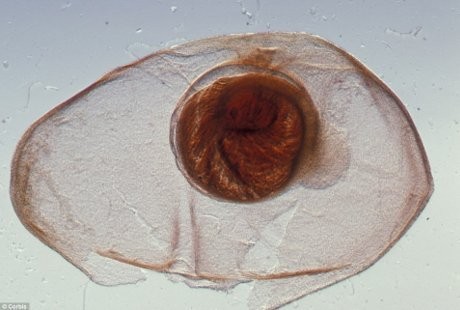

2. Otak Dipenuhi Larva Cacing Pita

(Foto: Corbis)

Telur cacing tersebut menyebar melalui makanan, air dan permukaan benda yang telah terkontaminasi dengan kotoran. Larva cacing pita tersebut kemudian melakukan perjalanan ke otak dan membentuk kista. Ketika mulai mati, larva menyebabkan aneurisma (kelainan pembuluh darah) sebesar ukuran jeruk tangerine di dalam otak Taylor.

Ibu empat anak ini harus dilarikan ke St George's Hospital, London, dan pemeriksaan MRI menunjukkan bahwa pembuluh darah di otaknya telah membengkak. Untuk menyelamatkan nyawanya, dokter bedah langsung melakukan operasi darurat dengan memasukkan shunt ke tengkoraknya untuk mengeringkan cairan di otaknya.

Taylor harus kehilangan kemampuan indera perasa dan penciuman karena kondisi tersebut. Pasca operasi, kini ia pun menderita epilepsi dan depresi.